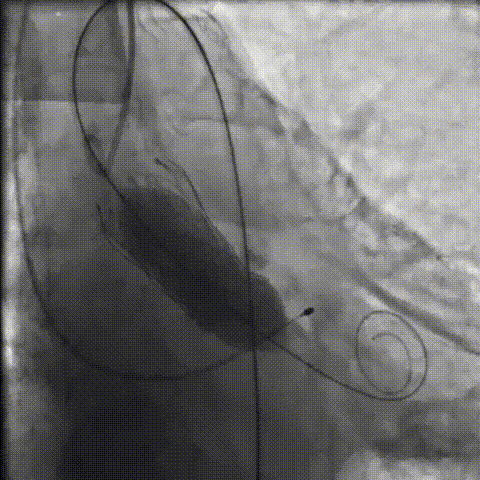

手术影像记录

主动脉根部造影

18mm球囊预扩

AV26瓣膜工作位造影

缓慢脱钩

23mm球囊后扩

后扩后造影:无漏